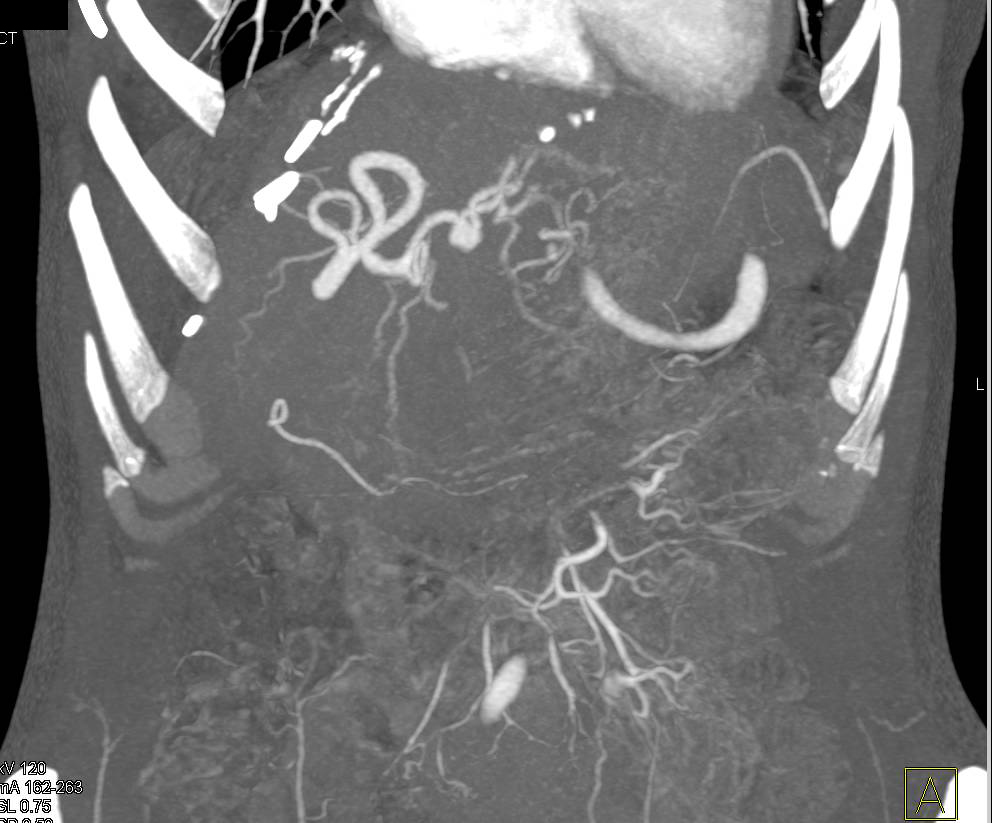

Recanalization of Umbilical Vein in a Cirrhotic Liver